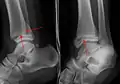

A triplane fracture of the ankle as seen on plain X-ray

- Triplane fractures are a special type of fracture that involves the immature skeleton. It has a coronal plane in the metaphysis, an axial plane in the physis and a sagittal plane in the epiphysis.[14]